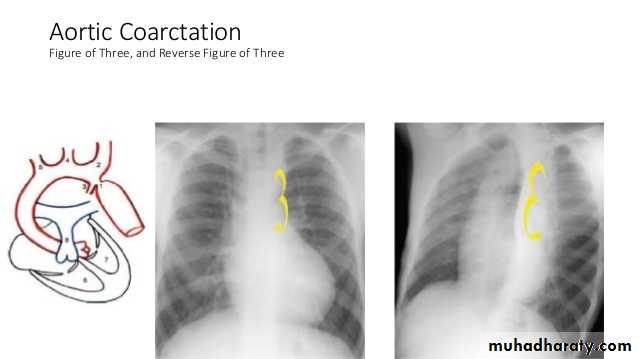

figure of 3 sign: contour abnormality of the aorta with inferior rib notching : Roesler sign in Coarctation of the aorta"box shape" heart in Ebstein anomaly